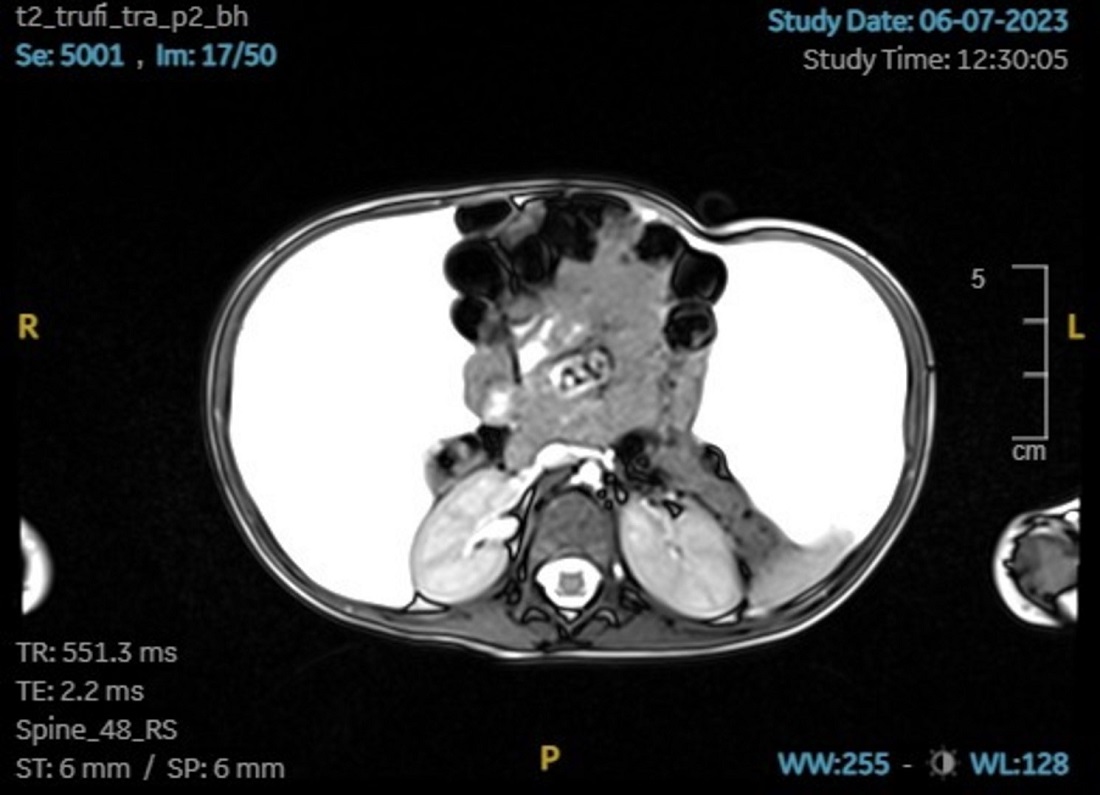

En la ecografía Doppler se observa gran cantidad de líquido libre peritoneal con ecos difusos en su interior y algunos tabiques. Se realiza resonancia magnética (RM) con los hallazgos que se muestran en las Figuras 1 y 2.

Figura 2. RM abdominal. Corte axial. Gran cantidad de líquido con desplazamiento central y anterior de todo el paquete intestinal, llegando a contactar las asas con la pared anterior abdominal. En la zona inferior presenta algún lóculo. No presenta aumento de intensidad de capas peritoneales tras la administración de contraste.